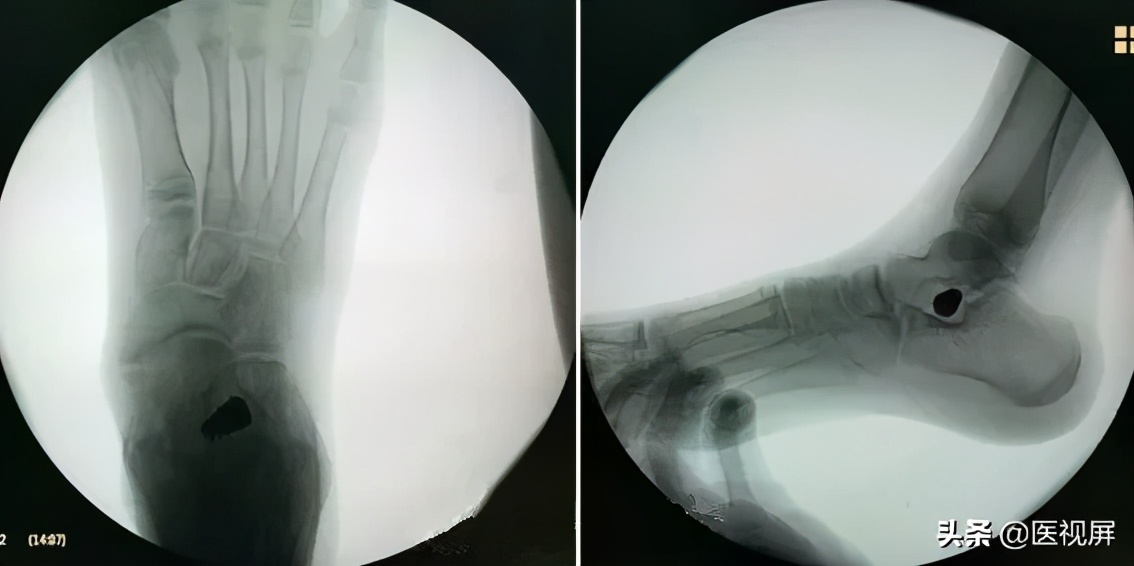

取出试模,打入相同大小型号的距下关节制动器。再次透视确认制动器位置(图6)。

▲图6 置入距下关节制动器

5.术后病例

女性12岁

行双侧距下关节制动术

术后一年随访:术后后跟内翻纠正,足弓抬高(图7)。

▲图7 术后病例